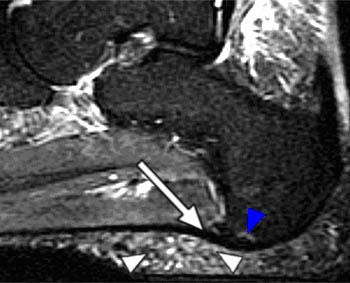

Plantar Fasciitis - Radsource

Plantar Fasciitis - Radsource from radsource.us